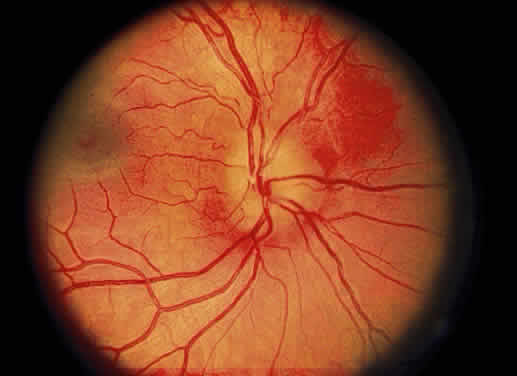

Cotton-wool spots are observed mainly in the posterior pole of the retina (Fig.23) The reason for this geographic restriction is not clear. Occlusion of the most superficial radially oriented peripapillary capillaries (confined in distribution to the posterior pole) has been implicated in the pathogenesis of cotton-wool spots.9 It is also possible that nerve fiber infarcts in the periphery are not visualized because there is insufficient inspissated axoplasmic material in this location.

Fig. 23. Multiple cotton-wool spots along with retinal hemorrhages in a superior temporal branch retinal vein occlusion.